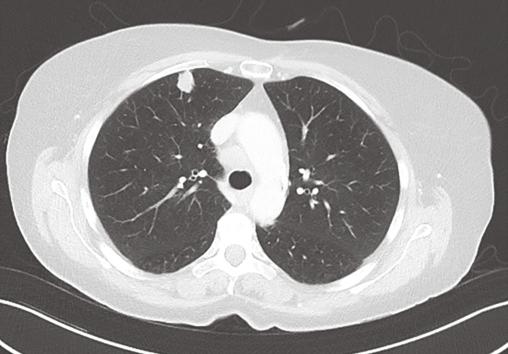

Une femme de 70 ans, tabagique sevrée à 45 paquets-années, présente un syndrome médullaire d’évolution rapide (3 semaines). L’imagerie par résonance magnétique montre une masse fusiforme intramédullaire au niveau de C7 (fig. 1 ). Le bilan lésionnel met en évidence un nodule pulmonaire évocateur de lésion néoplasique primitive (fig. 2 ), et plusieurs autres lésions secondaires : cérébrale, ganglionnaires et hépatiques. La biopsie hépatique confirme le diagnostic de carcinome pulmonaire (marqueur TTF-1 positif) métastatique peu différencié. L’évolution rapidement progressive a conduit à la mise en place de soins palliatifs exclusifs.